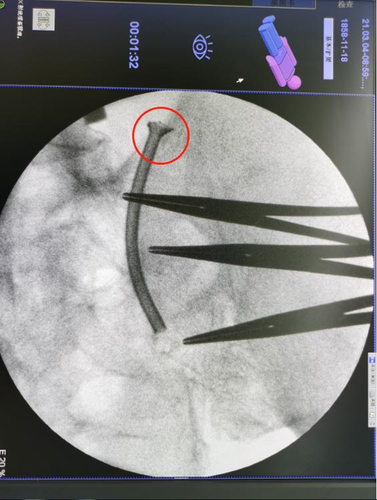

输尿管上接肾盂,下连膀胱,是一对细长的管道,呈扁圆柱状,管径平均为0.5~0.7厘米。输尿管有三个狭窄部:一个在肾盂与输尿管移行处(输尿管起始处),一个在越过小骨盆入口处,最后一个在进入膀胱壁的内部。这些狭窄是结石、血块及坏死组织容易停留的部位。输尿管出现变粗的情况,通常都是尿结石以及尿路感染造成的。

输尿管出现了扩张的情况,大多都是输尿管发炎导致的。其病变发生为腹膜后纤维组织增生,增生的组织包绕一侧或双侧输尿管。常见于输尿管肾盂交界处和髂血管分叉处。但也可以累及盆腔以上输尿管甚至肾脏由于纤维组织包绕输尿管导致输尿管狭窄,输尿管僵直,肾积水,两者需加以鉴别。此外,输尿管肿瘤和炎性狭窄也会造成输尿管扩张。